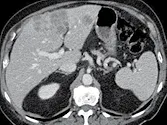

Figure 8. Carcinome hépatocellulaire. Sur l’examen initial (A, B), on observe

une lésion faiblement rehaussée au temps artériel (A), mais avec un lavage

évident au temps portal (B). Après six mois de chimiothérapie (C, D), la lésion est moins hypervascularisée au temps artériel (C), et de larges plages de nécrose sont apparues aux temps artériel et portal (D). La lésion est « PR » selon mRECIST